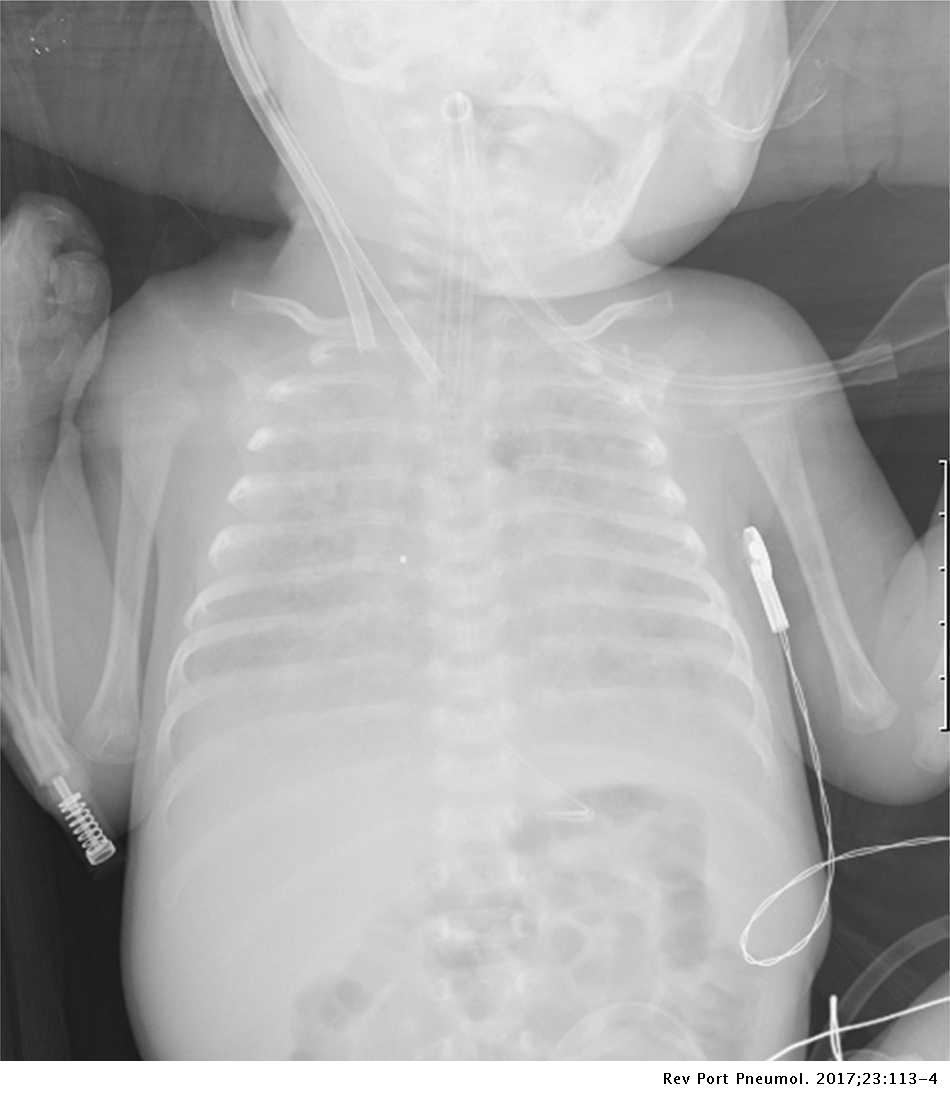

Figure1.Chest Xray showing diffuse reticulogranular shadows in the

Neonatal respiratory failure due to ABCA3 deficiency Pulmonology